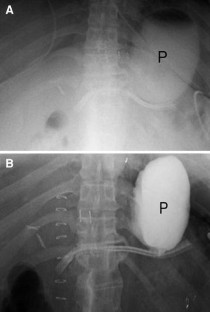

Fig. 1